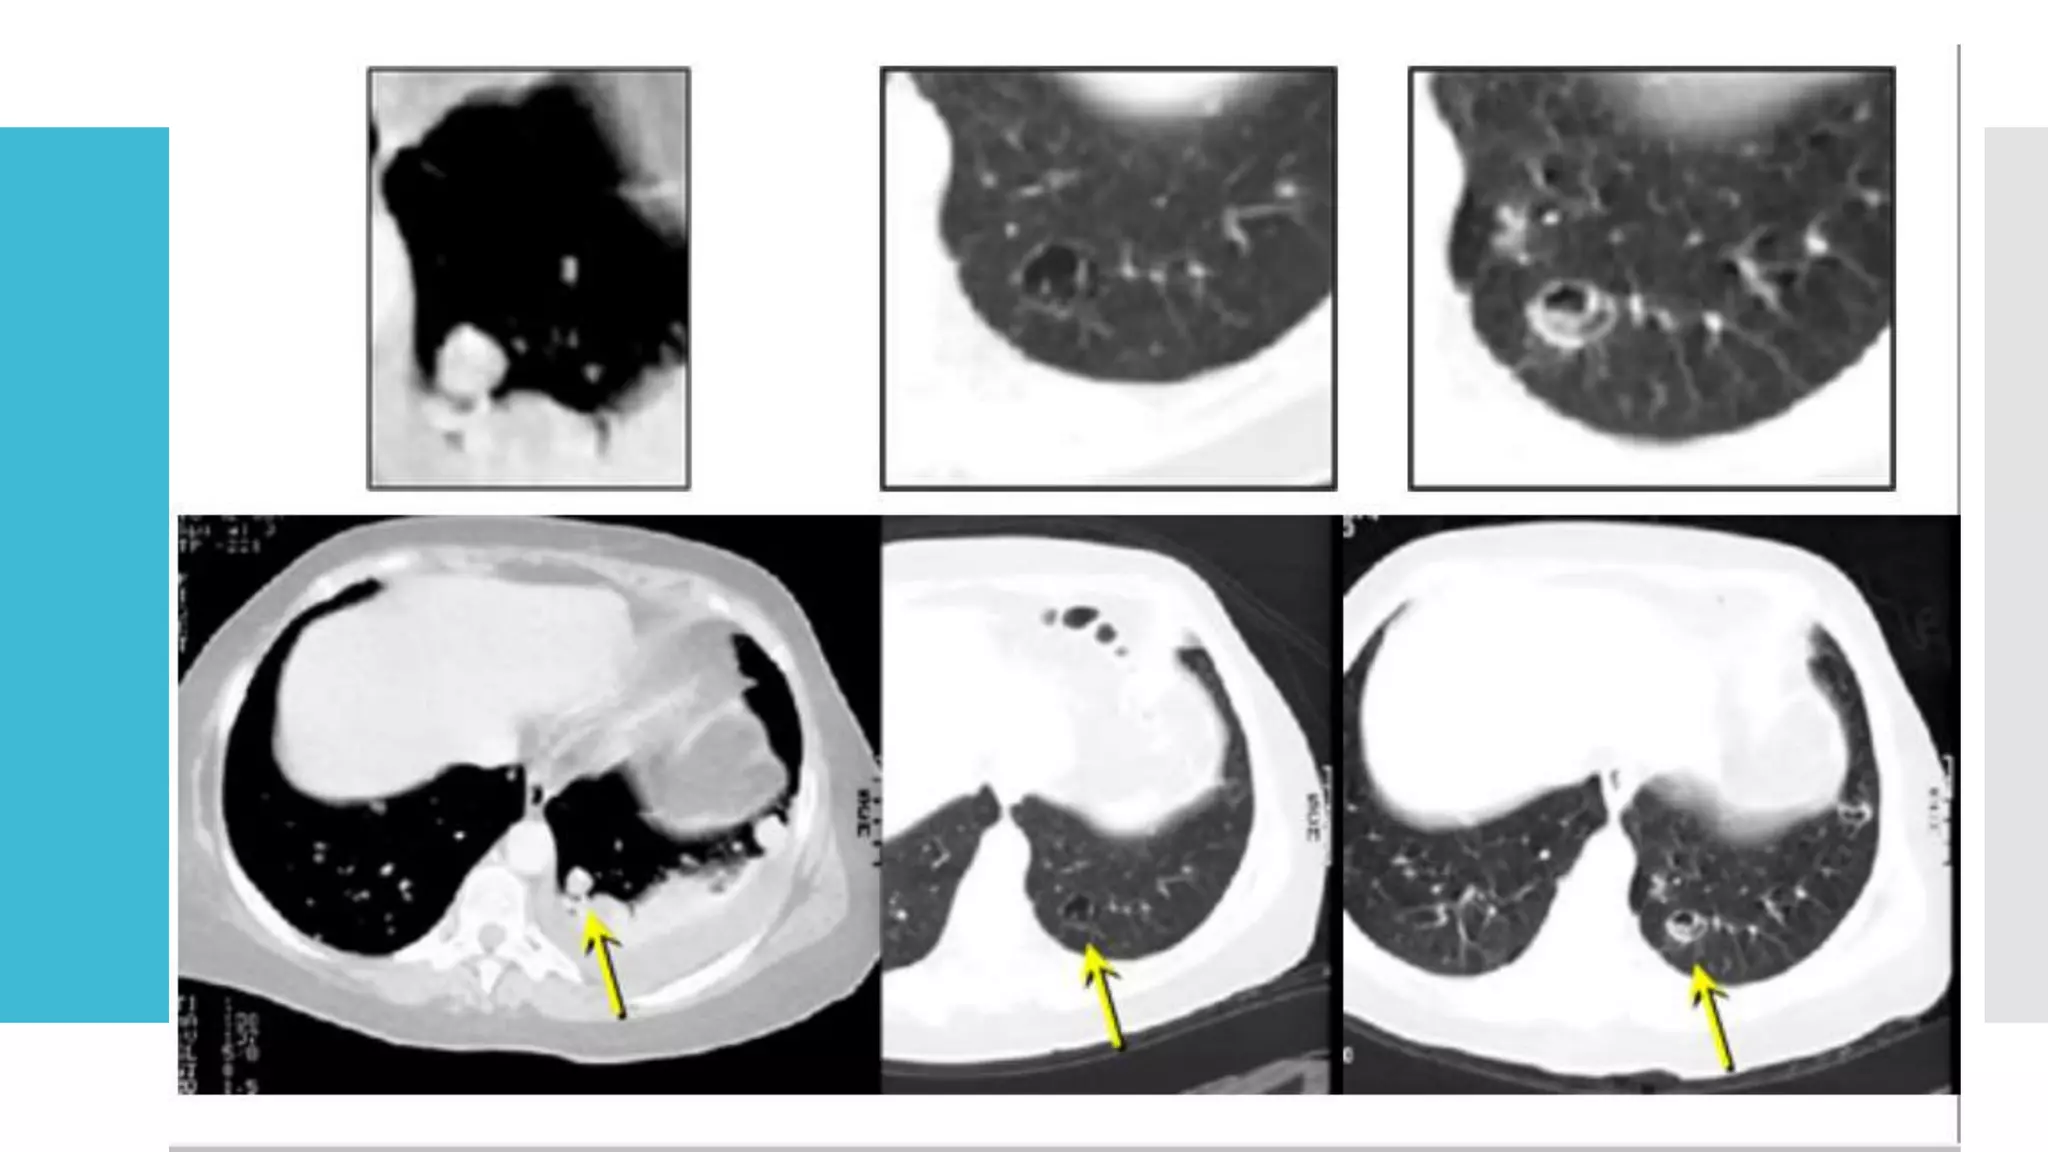

Lung Lesion develops cavity

 Continue measuring target lesions in their longest diameter,

even when they develop central cavities or necrosis.

Measuring in follow up. LungLesion develops cavity  Continue measuring target lesions in their longest diameter, even when they develop central cavities or necrosis.